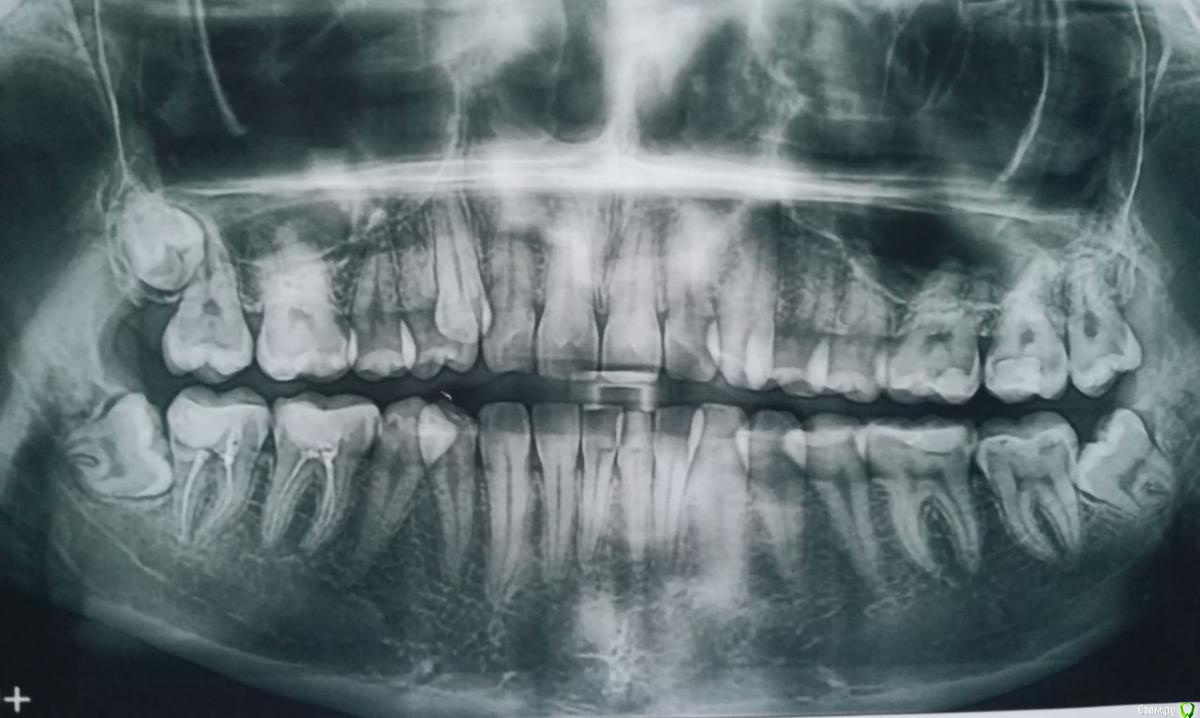

Tansky Опубликовано 18 марта, 2020 Автор Поделиться Опубликовано 18 марта, 2020 снимки - пара отпг до орто и актуальная, от 17.03.2020пара кт, в области интереса 3.6 и 4.7, разные снимки Ссылка на комментарий

Tansky Опубликовано 18 марта, 2020 Автор Поделиться Опубликовано 18 марта, 2020 разные проекции и описание заключения. прицельные rg есть еще по тому же зубу разных времен, но это надо искать дома и фоткать с негатоскопа или днем на свет Ссылка на комментарий